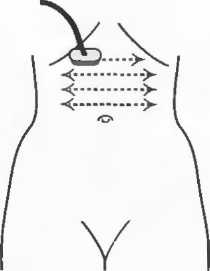

1. Подготовка

Пациент не должен пить и есть в течение 8 ч перед исследованием. Если жидкость необходима для предотвращения дегидратации, можно давать пациенту только воду. При острой симптоматике исследование можно проводить без подготовки. Детям, если позволяют клинические условия, пища и вода не даются в течение 3 ч до исследования.

При более углубленном исследовании, если нет клинических противопоказаний, может быть полезным дополнительный прием воды, особенно при исследовании поджелудочной железы, нижних отделов живота и таза.